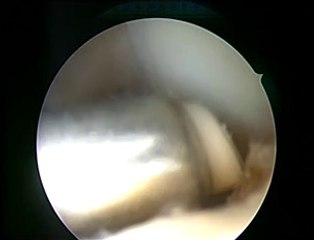

doctor ashfaq ahmed konchwala